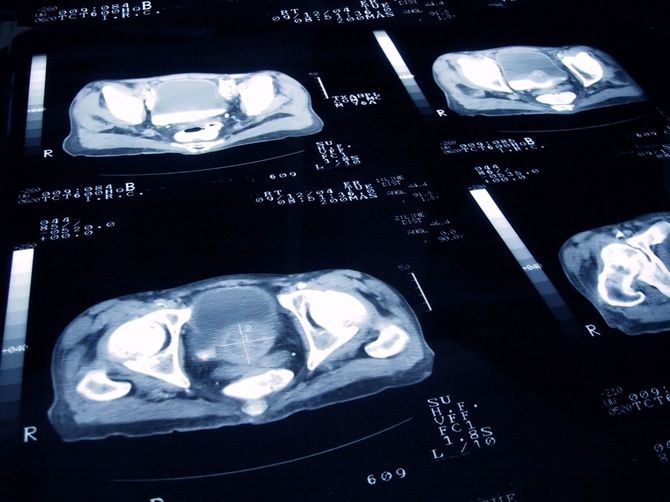

ところが、病院へ通い始めて3カ月ほどたった頃、熱発の原因は前立腺がんだったことが判明する。通院中の病院への不信感が募った母親が別の病院を探し、国立病院を受診したが、もうすでに手術はできないほどがんは進行していた。